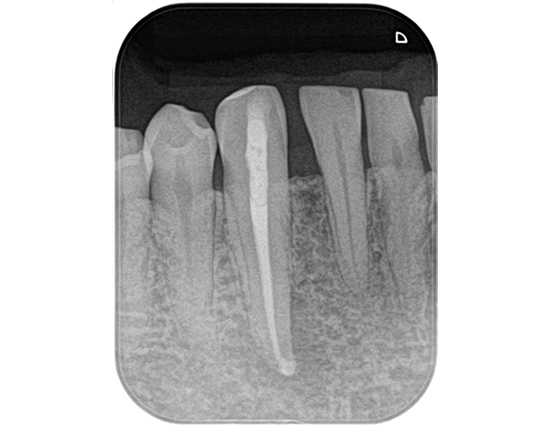

根管治療 症例 1

詳しく見る